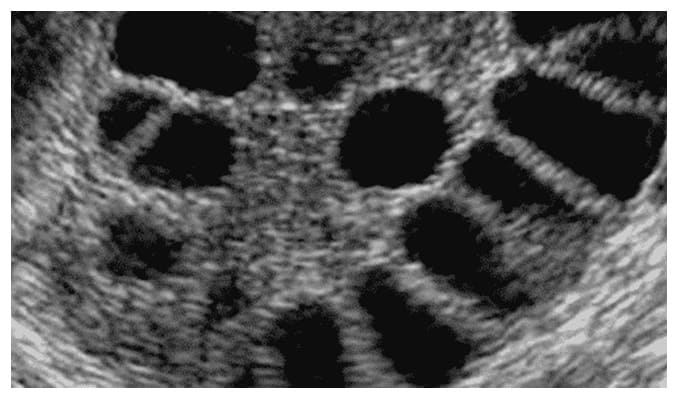

Presencia de múltiples quistes en los ovarios al ultrasonido.